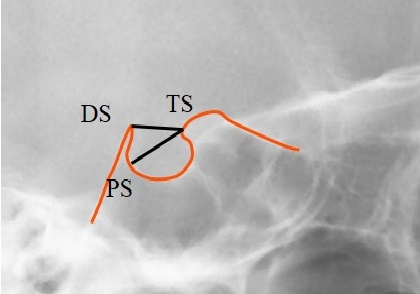

The pituitary fossa contour from the tip of Dorsum Sella (DS) to Tuberculum Sella (TS) was traced manually on an acetate paper using a 0.3 mm lead pencil in a dark room. A single trained examiner measured the length of the ST (distance between Tuberculum Sella and the tip of Dorsum Sella) and the greatest anteroposterior (AP) diameter (distance between Tuberculum Sella and the farthest point on the inner wall of the pituitary fossa) (Fig. 1) [2].

TS (Tuberculum Sella): The anterior boundary of sella turcica

DS (Dorsum Sella): The most posterior point on the internal contour of sella turcica

PS: The farthest point on the inner wall of the pituitary fossa